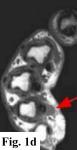

MRI FINDINGS:   MRI was performed on AIC's high-field 1.5 Tesla short-bore Siemens Symphony scanner using a small flexible surface coil. Fig. 1a is a high-resolution coronal DESS, Fig. 1b a sagittal T1 weighted, Fig. 1c a sagittal turbo STIR, and Fig. 1d an axial T1 weighted. They demonstrate a 5x5x7 mm nodule in the volar aspect of the hand at the level of the 4th MCP joint inseparable from the flexor digitorum superficialis tendon (arrows) with some adjacent soft tissue edema. The underlying tendon and bones are otherwise intact.

DIFFERENTIAL DIAGNOSIS:   Based on the MRI findings the DDX includes a benign soft tissue tumor such as a xanthoma, fibroma, hemangioma, neuroma or a lesion related to the tendon sheath such as a giant cell tumor of the tendon sheath or tendinous xanthoma. An inflammatory node was also in the differential. It does not have the MRI characteristics of a cyst or ganglion.

SURGICAL-PATHOLOGIC DIAGNOSIS:   The patient was taken to surgery at LCH by Dr. Rahmati and a "rather solid round mass attached to the volar aspect of the 4th tendon sheath" (arrows in Fig. 2a-b) was excised measuring about 4x4x3 mm. Pathology at LCH revealed a "grayish-white somewhat nodular smooth soft tissue measuring 9x8x5 mm" with histopathologic "features in favor of a giant cell tumor of tendon sheath" interpreted as benign.